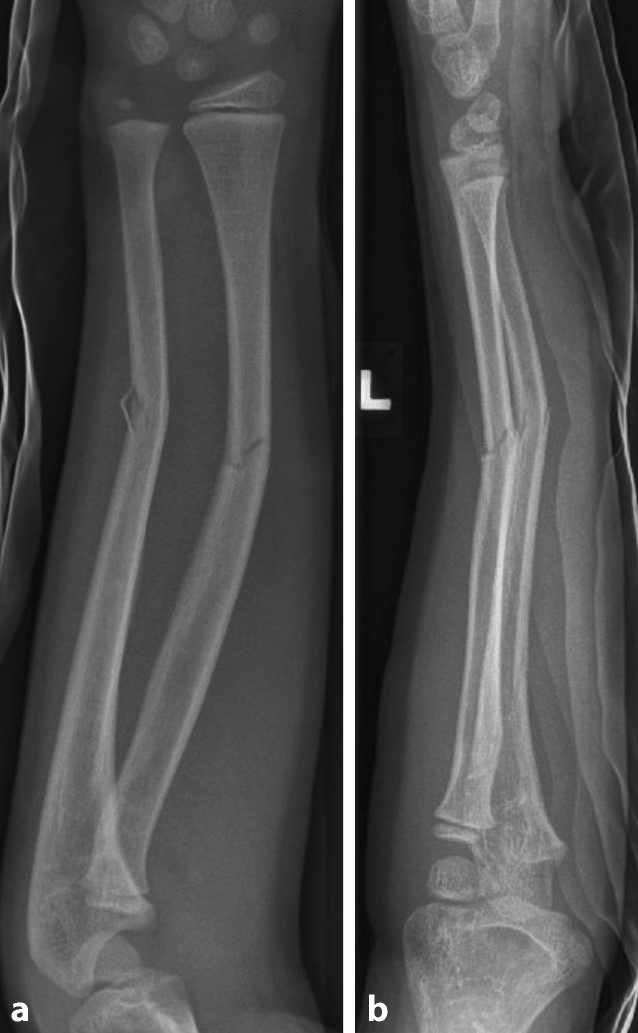

Abb. 2

Nach geschlossener Reposition und Gipsruhigstellung; Gegenkortikalis wurde nicht durchgebrochen. a seitliche Aufnahme, b a.p. Aufnahme

Abb. 3

Nach 4 Wochen Gipsruhigstellung gipsfreie Röntgenkontrolle; aufgrund inkompletter Konsolidierung weitere 6 Wochen Sportkarenz. a a.p. Aufnahme, b seitliche Aufnahme